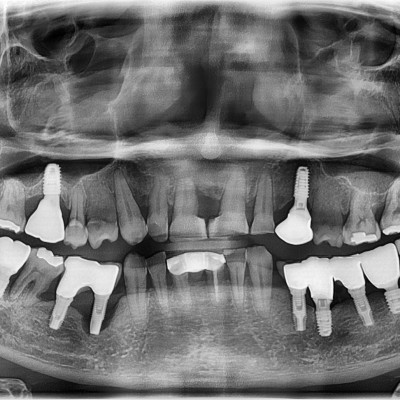

임플란트 재수술

임플란트 재수술 #24.25 타원임플란트 제거 후 임플란트 재수술 + 치조골 이식술 시행하였습니다.

작성자 이턱이 작성일 01-27 조회 128